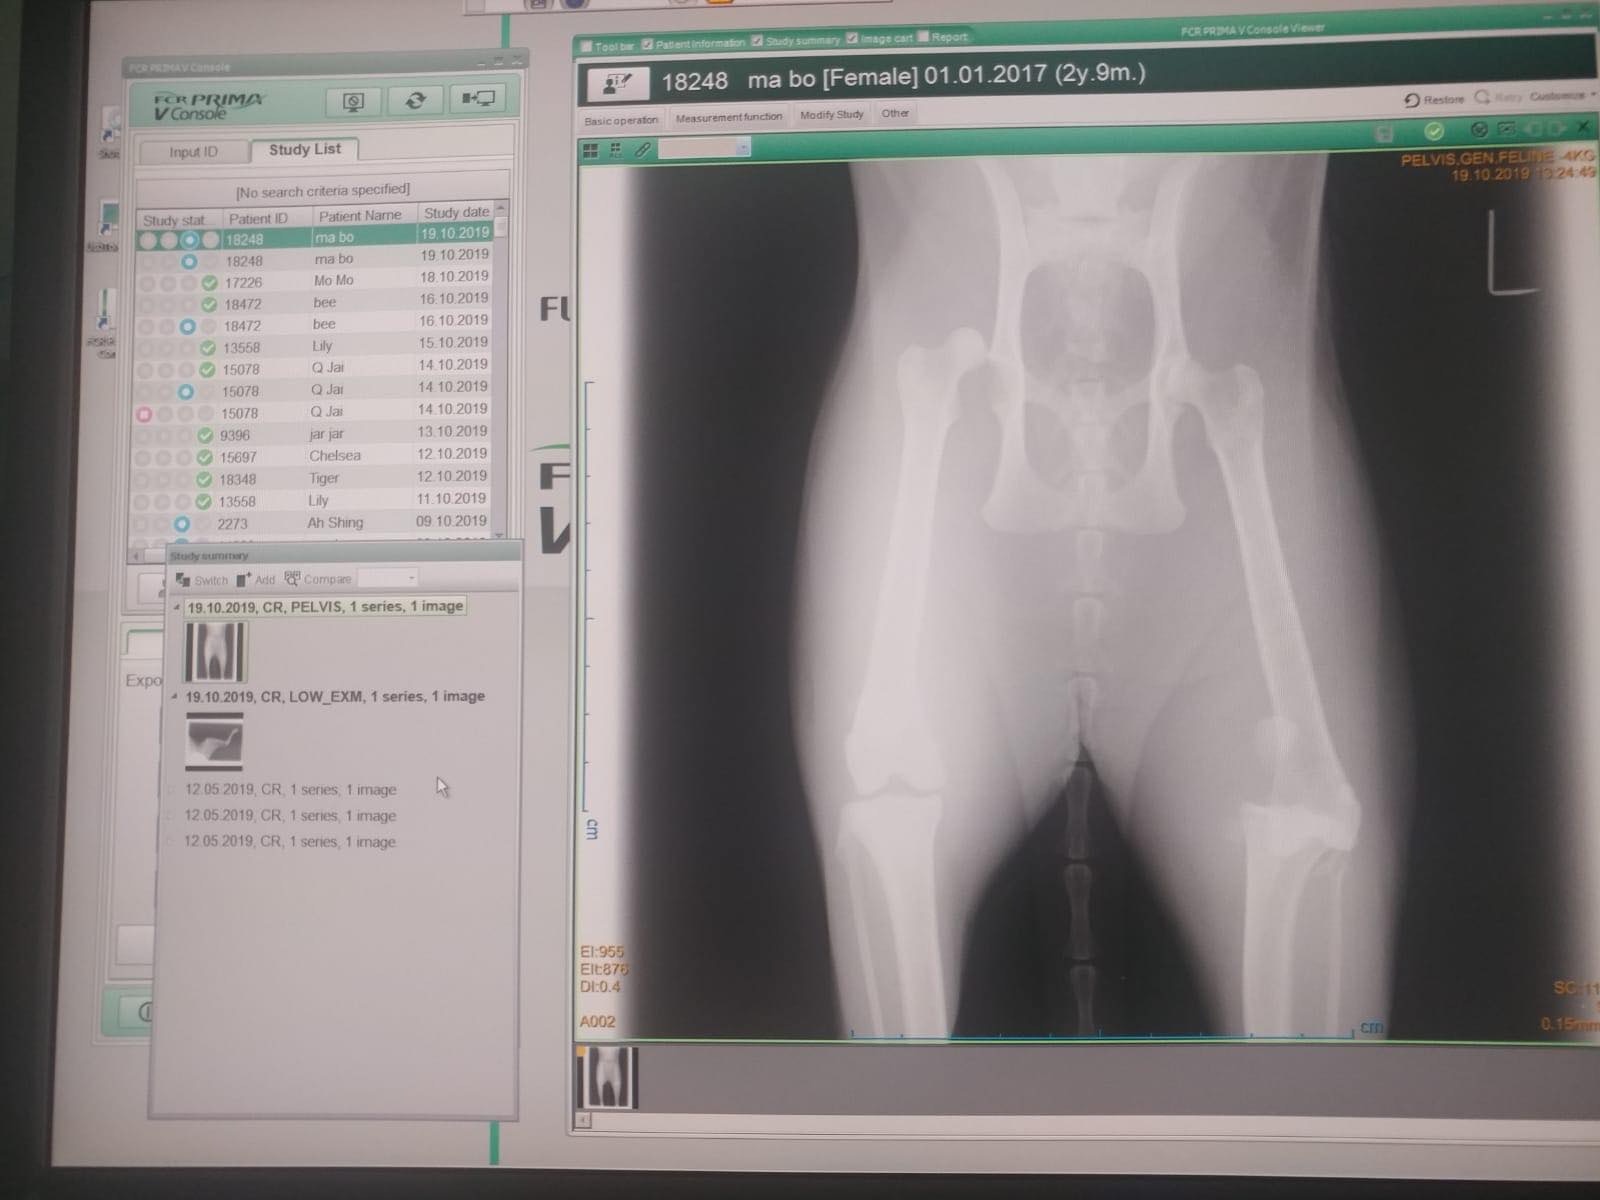

媽寶的下半身有多處嚴重受傷,膀胱有異樣,左腳骨折、膝蓋移位、韌帶斷裂,右腳盆骨脫骹。醫生先後兩次為牠做緊急手術,取出腹中的死胎,並治療膀胱、右腳,及後需要做第三次手術會再為牠的下肢做手術。